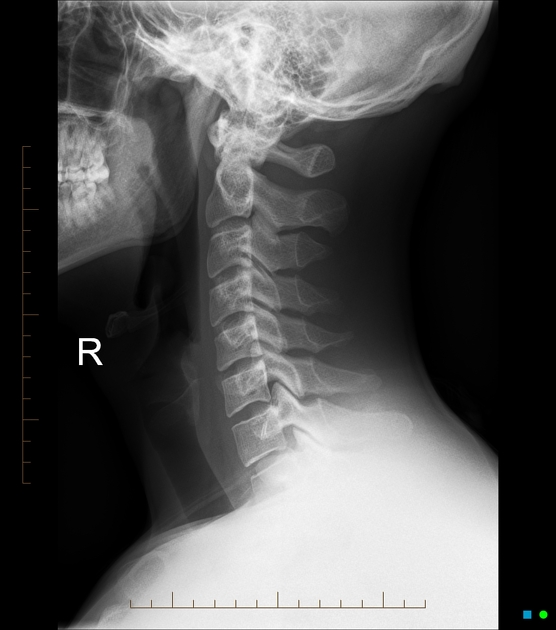

정상적인 경추는 C자 곡선을 이루어 머리 무게를 분산시킵니다. 그러나 거북목·일자목이 되면 머리가 앞으로 빠지면서 경추는 역학적으로 2~3배 무거운 하중을 받습니다.

- 사무직 직장인 A씨: 하루 10시간 컴퓨터 업무 후 뇌검사에서는 이상 없음. 그러나 X-ray상 C커브 소실로 진단 → 물리치료와 운동 후 호전.

- 정확한 진단: MRI·X-ray로 목 구조 확인, 필요시 신경차단술